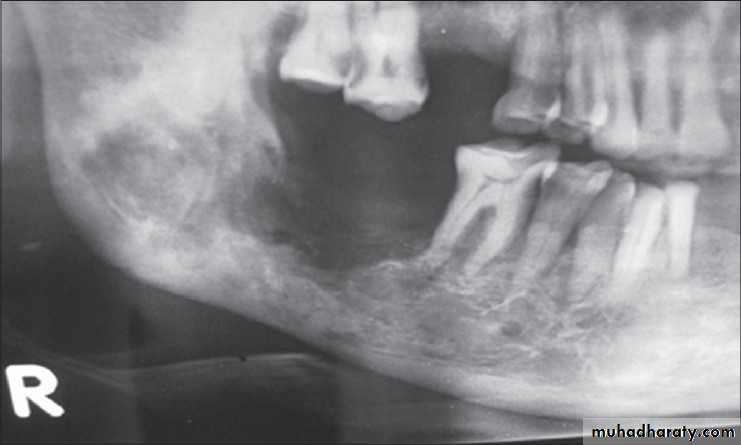

(1) Extraction of the teeth.(2) Removal of the associated interseptal bone.

(3) Collapse of the labial cortical plate of bone and mucoperiostium, back into the resulting ‘ gutter‘.

18

(4) Insertion of the clear acrylic template to check if bone removal has been sufficient. Blanching of the mucosa is clearly seen beneath the template in any area where there is excessive pressure.

Goals of alveoloplasty

Eliminate bony projections that result in undercutsImprove the path of insertion of the prosthesis

Eliminate bony sources of irritation